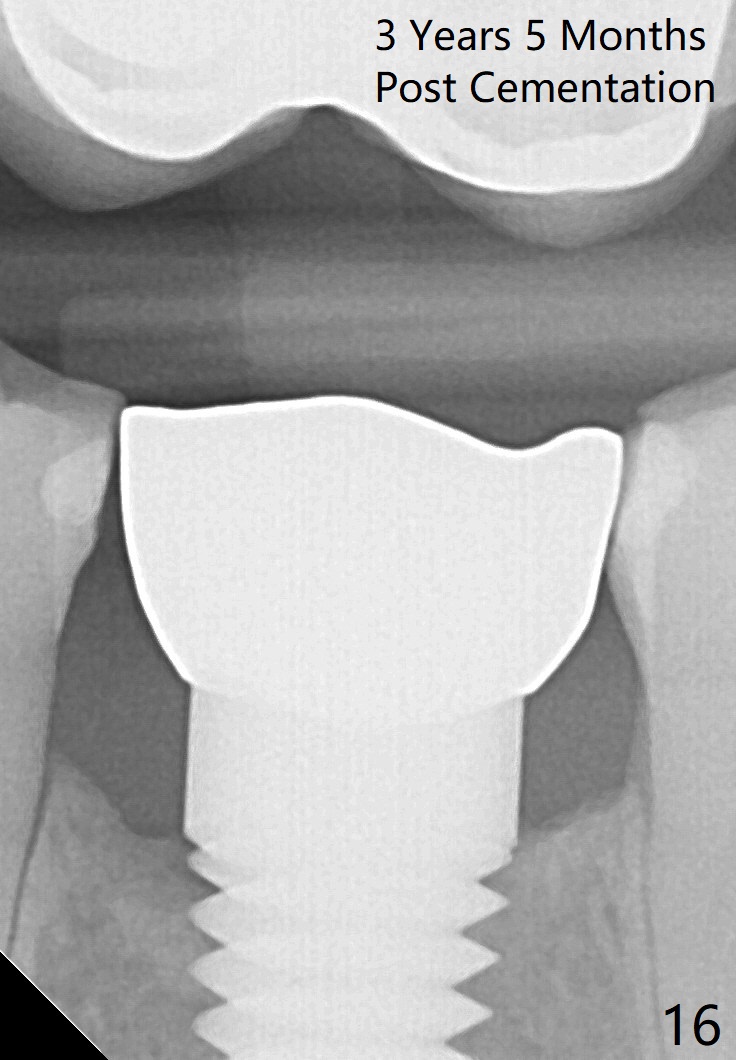

Eleven months post bonding (17 months postop), there is cortical bone formation at the mesial and distal crests (Fig.14). It remains the same 1 year 10 months post bonding (Fig.15). There is no bone loss 3 years 5 months post cementation (Fig.16). In fact the crestal cortical bone thickens.